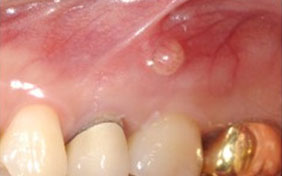

뿌리 끝에 염증이 생겼으나 치근단절제술을 할 수 없는 경우

의도적 재식술로 치아를 살릴 수 있는 경우

뿌리끝에 염증이 생겨 옆으로 튀어나온 모습입니다. 재식술에 의해 치료 후 원래의 치아를 계속 사용합니다.